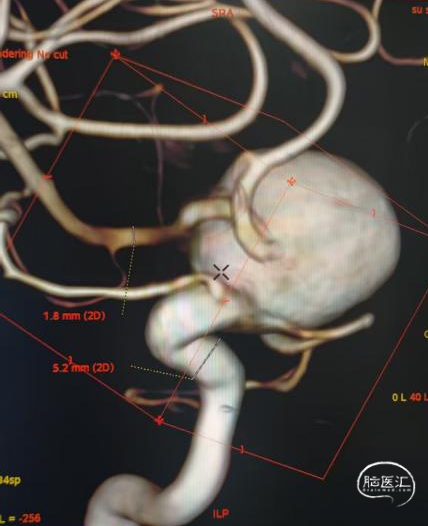

术前影像

脑动脉DSA提示右侧颈内动脉C5床突段动脉瘤。

右侧床突段载瘤动脉远端血管直径为1.8mm,载瘤动脉近端血管直径为5.2mm,瘤体宽13.1mm,瘤体最大宽度21.8mm。